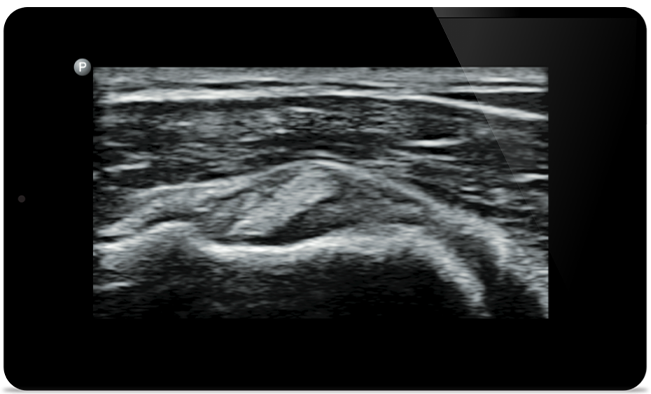

Lumify помогает визуализировать мелкие детали мышц, суставов, связок, сухожилий и хрящей, чтобы поставить более точный диагноз при травмах.

Lumify поможет вам обследовать пациента с головы до ног независимо от диагноза, будь то плантарный фасциит, тендинит или бурсит надколенника или даже нестабильность вращательной манжеты плеча.

SonoCT улучшает визуализацию настоящих тканей, устраняя случайные артефакты. Эта технология позволяет получать изображения, превосходящие по качеству обычные изображения, у 94% пациентов.